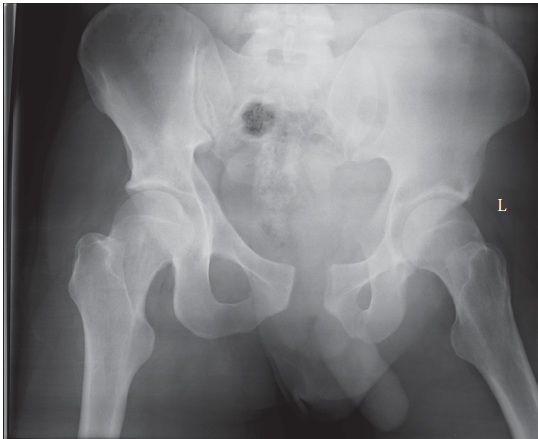

What does this radiograph show and how would you classify this injury? This is an AP radiograph of the pelvis…